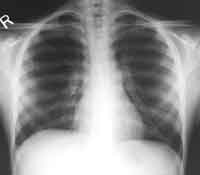

A chest radiograph was performed.

Enlarge the X-ray on your LEFT, enlarge the X-rray on your RIGHT

WHAT IS YOUR INTERPRETATION?